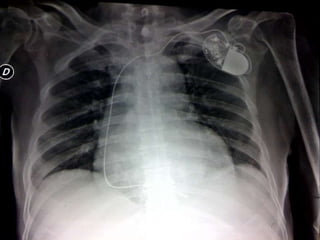

CARDIOPULMONAR:

Ruidos cardiacos rítmicos, no se auscultan soplos,

disminución del murmullo vesicular basal, disneico

Se observa tumefacción en hemitórax anterosuperior izquierdo

correspondiente a marcapasos

22/09/11

• Deterioro

– Disnea, dolor torácico irradiado a

espalda, desaturación, no fiebre

– Alerta, mal estado general, disneico, orientado

– TA 69/36 FC 60 FR 24 SAT 96% FIO2 0.50 TEMP

36.7